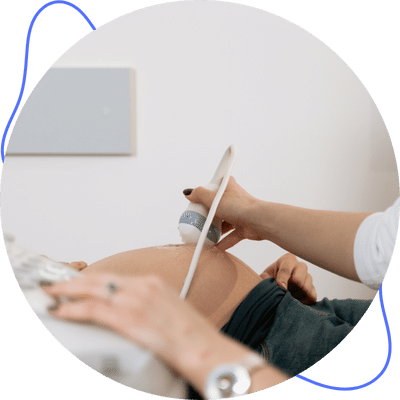

Obstetricia

Ginecología y Obstetricia en el Hospital de Ginecología y Obstetricia Número 4 "Luis Castelazo Ayala" IMSS en la Ciudad de México.